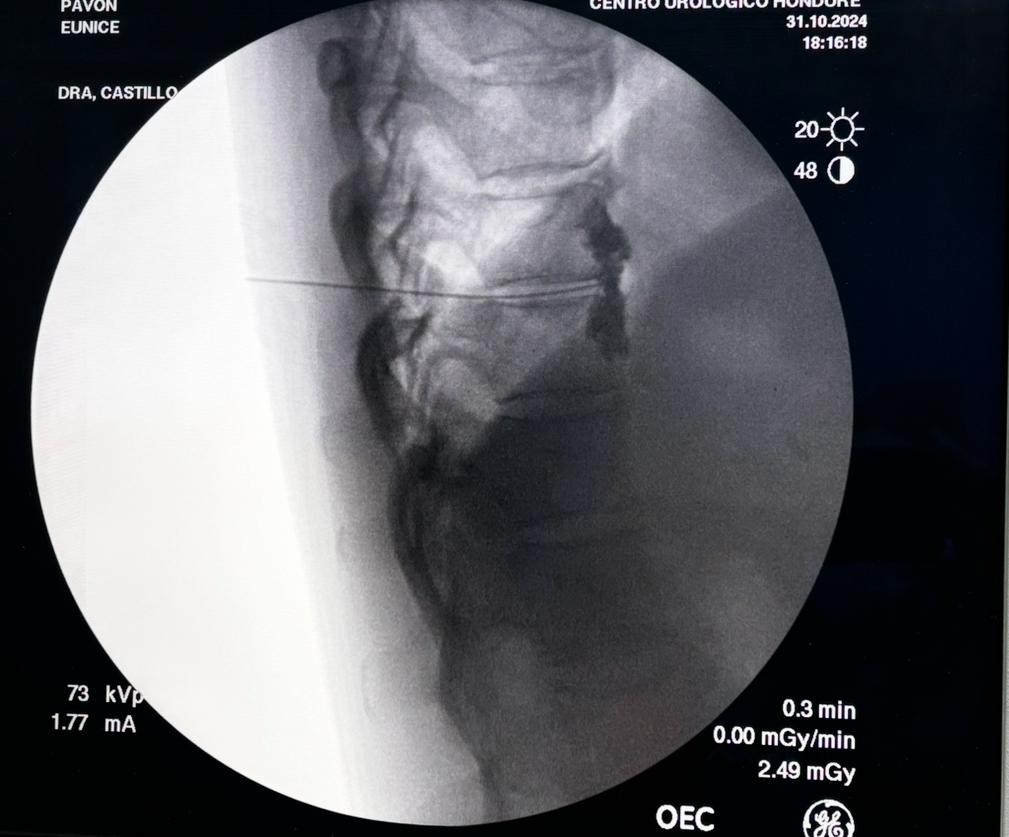

Radiofrecuencia pulsada , ganglio de la raíz dorsal en neurálgico posherpetica